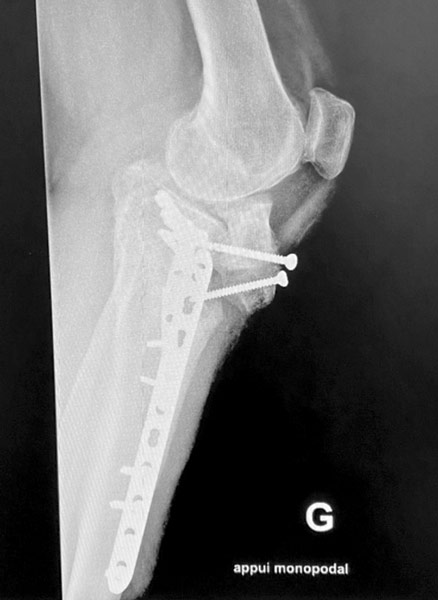

Patiente opérée à l’âge de 30 ans d’une rupture du ligament croisé antérieur. Arthrose progressive. Handicap important.

2ème opération à l’âge de 40 ans, du fait d’une arthrose interne du genou, par ostéotomie tibiale de valgisation. Excellent résultat 10 ans après

10 ans après l’ostéotomie, excellent résultat : aucune douleur, mobilités normales.